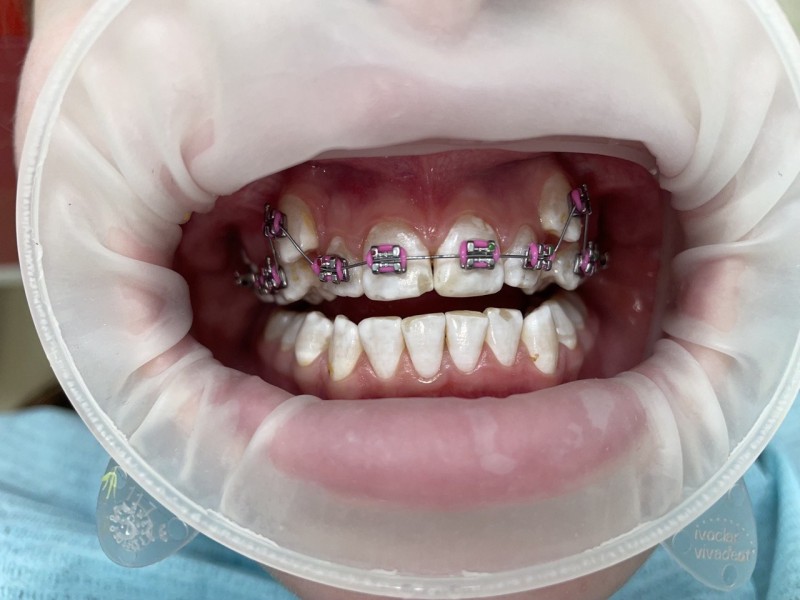

Установка металлических брекетов

Большой дефицит места на верхней челюсти в следствие чего произошло искривление зубов. Срок лечения 1 год и 5 месяцев. Металлическая брекет-система.

Доктор: Хачатрян Лариса Рубеновна